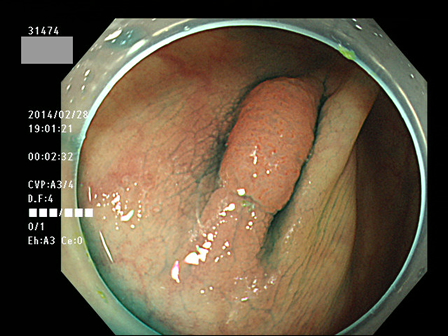

上記100名より抽出した平坦・陥凹型腺腫(=癌化の危険が高いが見落としやすい病変)の内視鏡写真